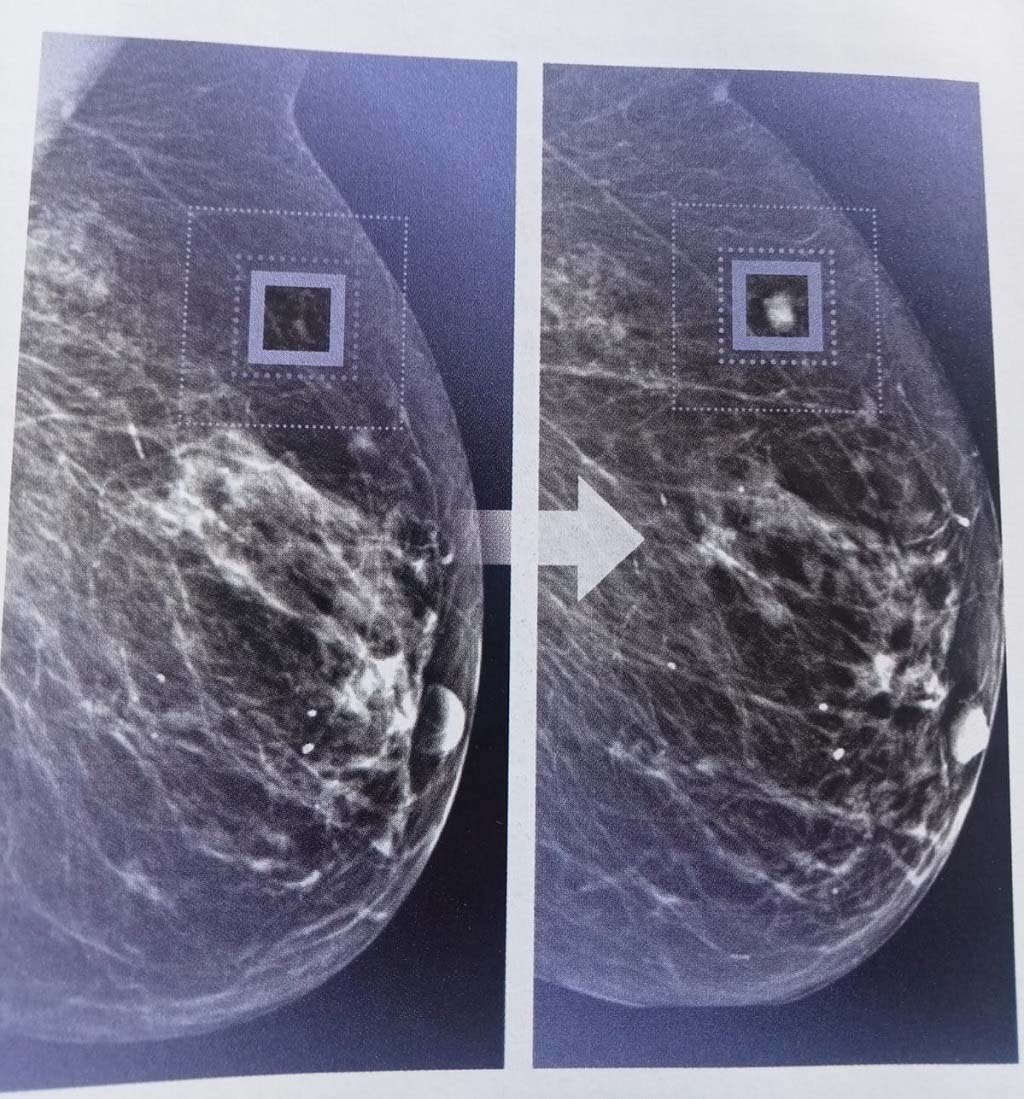

Un algorithme mis au point récemment a démontré qu’il était capable d’identifier chez une femme un risque de cancer du sein (voir tache dans l’encadré à droite) quatre ans avant qu’il soit visible sur les radios prises lors d’une mammographie traditionnelle (voir celle qui est dans l’encadré de gauche).

Prenons l’exemple du diagnostic précoce du cancer du sein. Disponibles en grand nombre, les radiographies permettent d’entraîner l’IA à détecter les anomalies les plus infimes.

En intégrant les données fournies par des dizaines de milliers de mammographies, des organismes comme le Massachusetts Institute of Technology (MIT) ou la société niçoise Therapixel ont mis au point des algorithmes capables de traquer les images suspectes bien avant que les signes de développement tumoral ne soient perceptibles par l’œil humain.